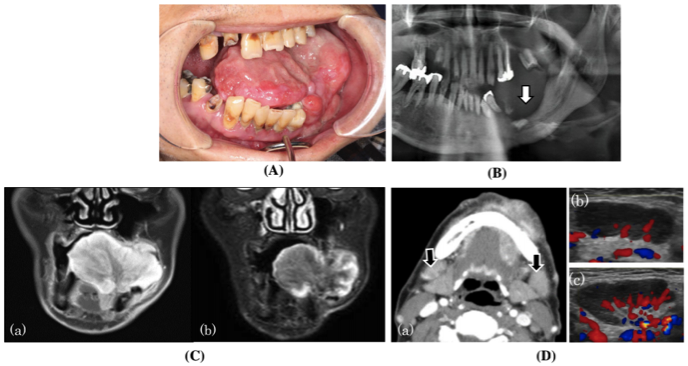

一名60岁的日本男子因左侧口腔内肿瘤疼痛且肿大,前往口腔颌面外科就诊。约65mm×45mm的有蒂肿瘤位于左下牙槽区。肿瘤表面为肉芽肿,弹性硬,部分溃疡,出血。肿瘤使舌头向右移位(图1A)。下牙槽神经支配的区域没有感觉减退。口腔卫生较差。在双侧下颌下区触诊到拇指尖大小的活动性弹性软肿淋巴结。患者既往有食管裂孔疝和反流性食管炎病史,无哮喘和过敏。没有特别相关的家族史。患者身高160cm,体重53kg。注意到由于肿瘤导致的进食困难,患者的营养状况较差。

图1. 患者的状态

全景X线和计算机断层扫描(CT)均显示左下颌骨压缩性骨吸收,但皮质骨保留(图1B)。据此认为,病变的长期持续生长导致了压缩性骨吸收。T1加权钆增强磁共振成像(T1-Gd-MRI)显示整个肿瘤,尤其是肿瘤边缘有显著对比。使用短T1反转恢复(STIR)扫描检测到高边缘强度(图1C)。正电子发射断层扫描(PET)-CT扫描显示肿瘤区域内氟脱氧葡萄糖的高累积,最大标准化摄取值(SUVmax)为5.7。颈部淋巴结的CT扫描显示,左侧和右侧下颌下区均有肿大的淋巴结(分别约25 mm和20 mm),右侧肿大的淋巴结显示高对比度。颈部回声证实肿胀的下颌下淋巴结平坦,边缘光滑。尽管在肺门区域观察到局部血流增加,但淋巴结肺门清晰可见(图1D)。PET-CT扫描显示双侧下颌下淋巴结内有积聚,左右两侧SUVmax值分别为3.9和3.0。